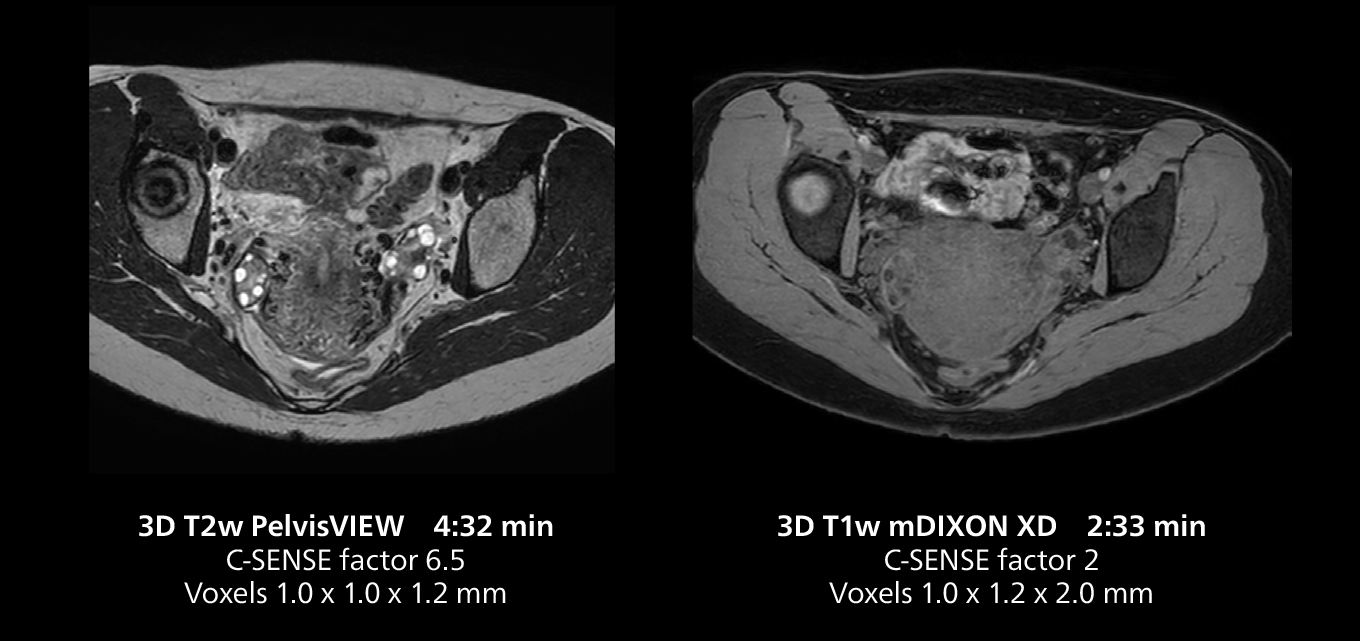

Female pelvis imaging

This MRI case illustrates good resolution and imaging quality obtained within reasonable scan times using the MR 5300 1.5T system with the anterior torso cardiac coil that allows use of a large field of view (FOV).

Free-breathing scans provide reproducibility and patient comfort

Dr. Gellée highlights the robust free-breathing scans as “the feature that makes the biggest difference in my daily work. The 3D free breathing sequences are very reproducible, and the axial acquisition is very good. For example, in endometriosis, which is one of my focus areas, it provides high contrast and good resolution so that I can see small details. We also use free breathing for liver and pancreas imaging. In multi-phase liver studies, 4D Free Breathing delivers 3-second temporal resolution, making a dynamic scan with more than one arterial phase possible.”